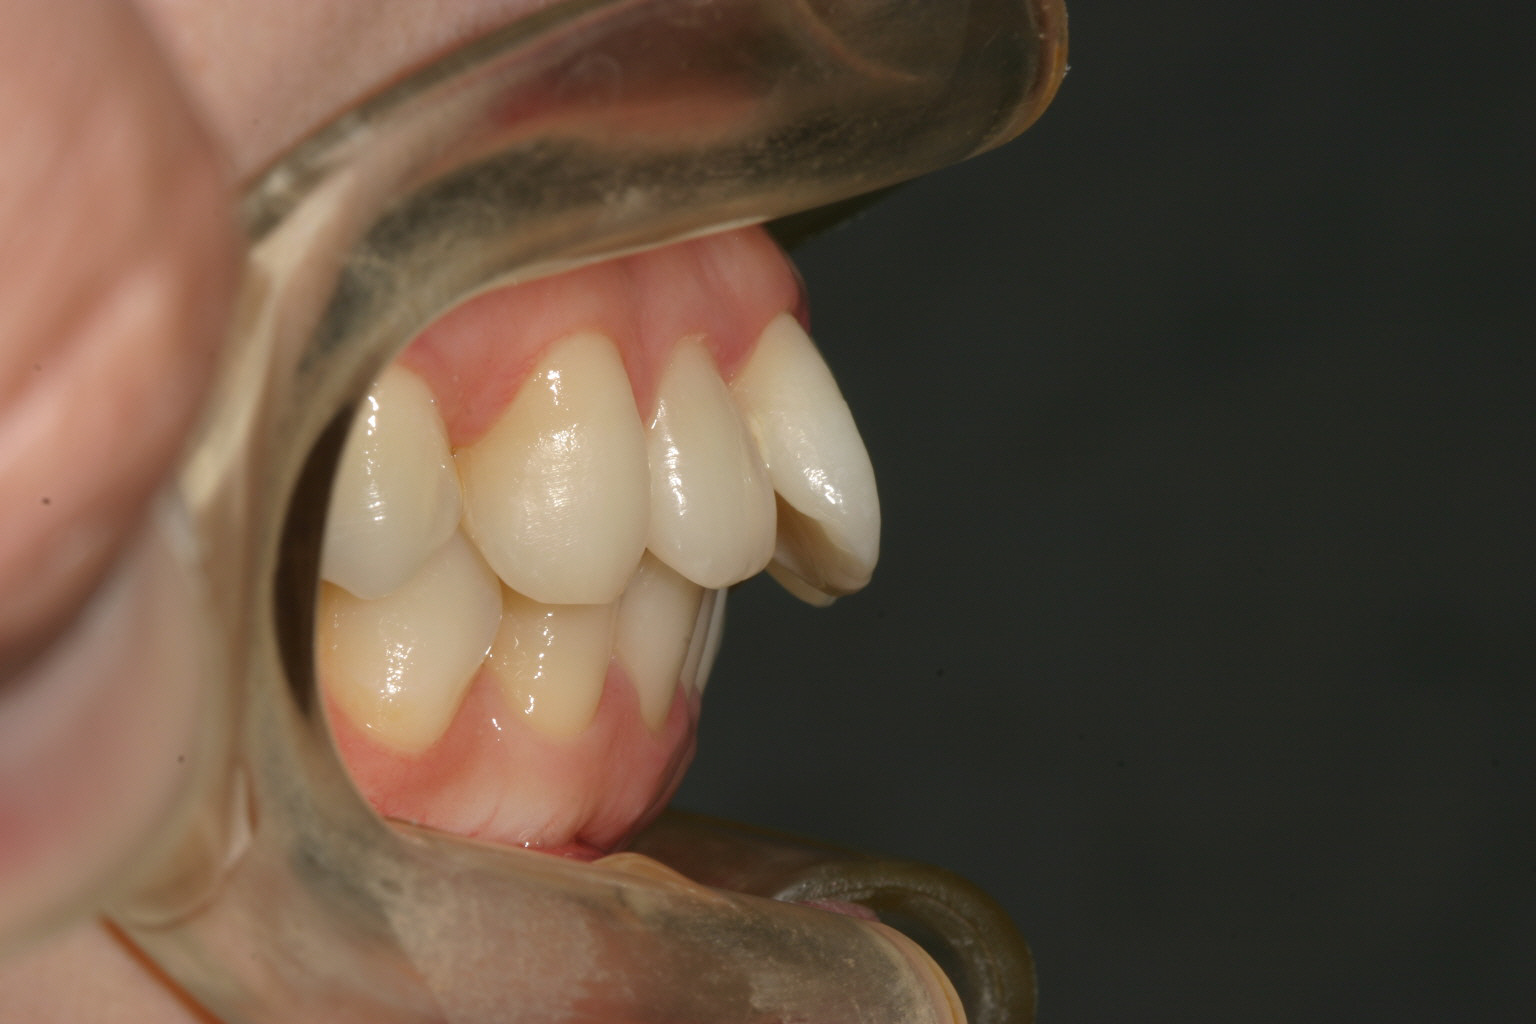

非抜歯でアーチも拡大され翼状捻転も改善しました。

下顎も非抜歯でこの様に綺麗なアーチになりました。

抜群のオーバージェットが得られました。